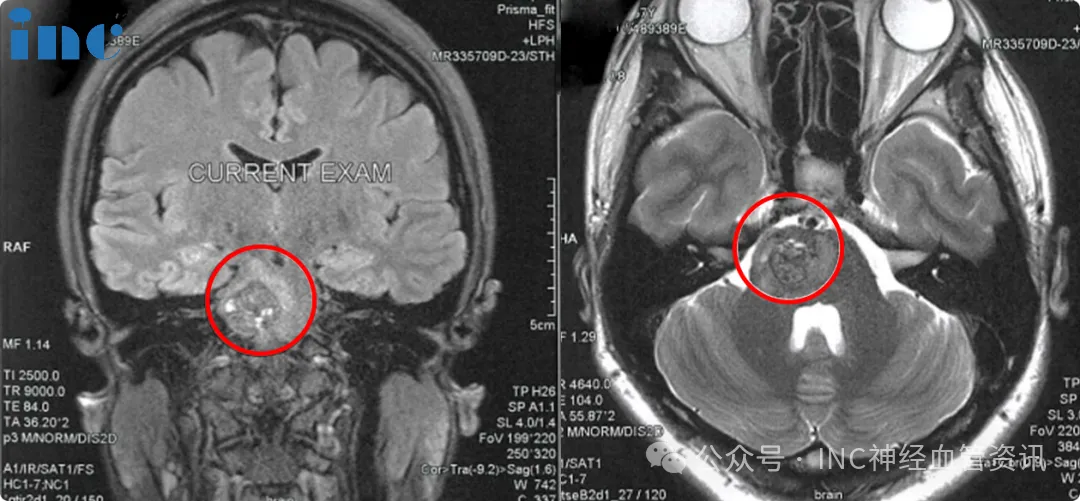

一切始于一个平常的夏日,佩珊突然出现左侧肢体无力,左脚症状尤为明显。香港当地医院的颅脑MRI检查明确诊断为脑干桥脑海绵状血管瘤出血。

手术顺利完成,病灶全切且未出现面瘫、偏瘫等并发症,无需放疗辅助。术后第三天佩珊即可自如行走,最新MRI复查证实病灶已完全切除。